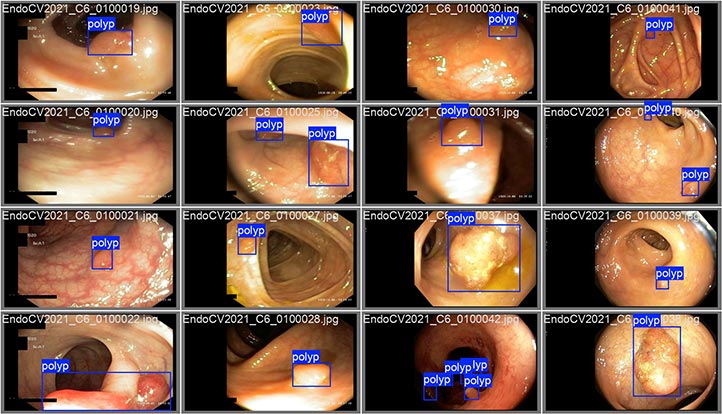

La IA apoya la detección de pólipos realizada mediante una colposcopía

En la actualidad han comenzado un nuevo proyecto, enfocado en la detección de pólipos colorrectales, dado que el cáncer colorrectal es la segunda causa de muerte a nivel mundial entre hombres.

“La forma en la que se hace la detección es a través de un colonoscopio, una cámara que se introduce en el colon; no obstante, aproximadamente un 20% de los pólipos no se detectan, entonces consideramos que, si se tiene un sistema de apoyo, es como un segundo ojo que está viendo la misma imagen”.

El investigador puntualizó que la idea es detectar a tiempo los diversos tipos de pólipos y determinar si son malignos o benignos, aplicando las técnicas de visión por computadora, específicamente en el área de imagenología médica.